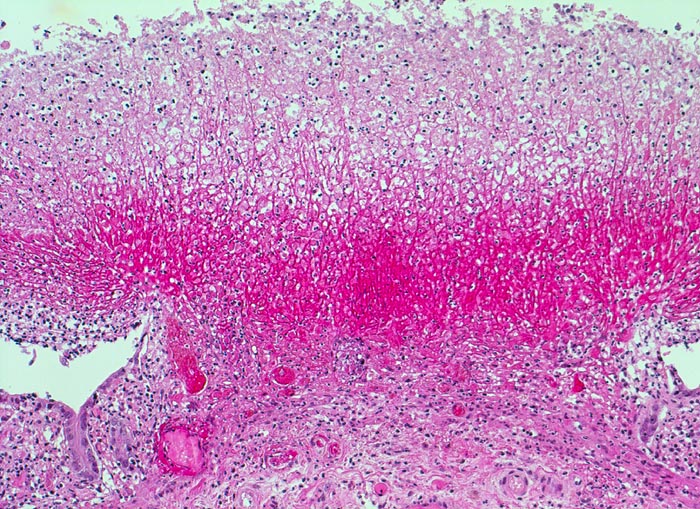

pseudomembranöse Kolitis

Pseudomembran aus roten Fibrinfäden, Detritus und Entzündungszellen auf einem oberflächlichen Schleimhautulkus. Die angrenzende erhaltene Mukosa zeigt einen Becherzellverlust und ein basophiles Epithel mit vergrösserten Kernen im Sinne einer ischämischen Schädigung.

Schwere Diarrhoe, Fieber, Erbrechen, krampfartige Bauchschmerzen 4 Tage nach Beginn einer Antibiotikatherapie mit Ampicillin. Im Stuhl Nachweis von Clostridien Toxinen. Endoskopisch typisches Bild mit erhabenen gelben Plaques auf der Mukosa.

Echte Membranen bestehen aus einem Epithel, deshalb der Ausdruck Pseudomembran für die Auflagerungen aus Fibrin, Detritus und Entzündungszellen bei der pseudomembranösen Kolitis.